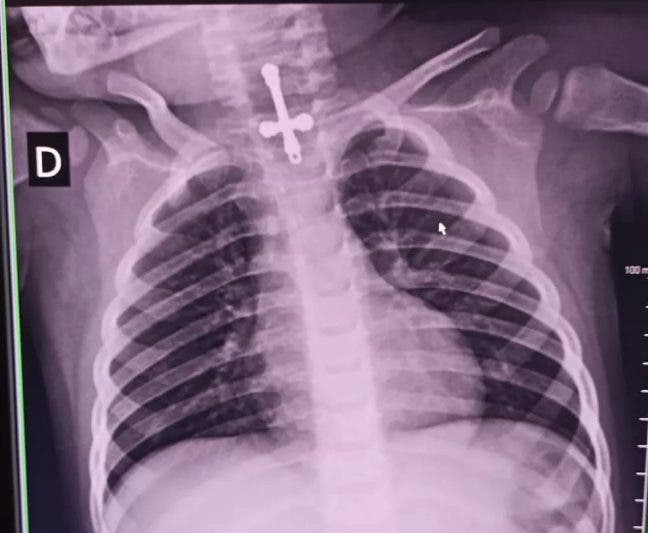

Un pequeño de dos años fue llevado de urgencias al Hospital de Passos, en el sur de Minas, permaneciendo hospitalizado tras ser sometido a una intervención médica para extraerle un crucifijo que se tragó el pasado sábado 17 de octubre.

El objeto obstruyó el aparato digestivo del menor, quien fue ingresado en la Unidad de Emergencias (UPA) de Divinópolis. En el sitio, esperaba un traslado a una unidad de alta especialidad en el municipio de Passos, lo que ocurrió el lunes 19.